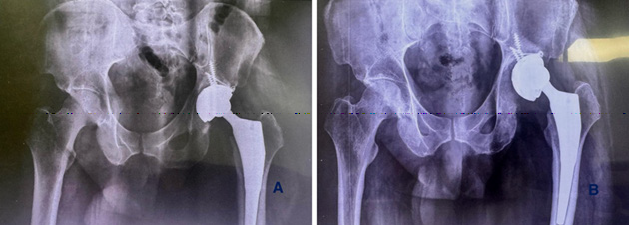

Postoperative recovery was uneventful. The patient was mobilized with toe-touch weight-bearing using a walker on the first postoperative day. At one-year follow-up (Figure 4), the patient showed marked improvements in pain relief, hip range of motion, and functional status, with a significant increase in the Harris Hip Score (Figure 4).

The patient gave written, informed consent to have this case report published. The patient was a 52-year-old male who presented with progressively worsening left hip pain and increasing difficulty in ambulation. He had undergone a Total Hip Arthroplasty (THA) elsewhere for Avascular Necrosis (AVN) secondary to a femoral neck fracture. Within two months of the primary surgery, radiolucent lines began appearing around the acetabular component. By five months, his symptoms had significantly worsened, and repeat radiographs revealed abduction failure and loosening of the acetabular cup across all three DeLee and Charnley zones (Figure 1).

Reconstruction was carried out using a press-fit TMARS™ (Trabecular Metal Acetabular Revision System) (Zimmer Biomet Warsaw, Indiana, USA) shell secured with multiple screws, including a kickstand screw for added stability. A cemented Evolutis Dual Mobility polyethylene liner was implanted, and femoral reconstruction was performed using a 14 mm × 225 mm Wagner revision stem (Zimmer Biomet Warsaw, Indiana, USA). Following final reduction, the construct demonstrated excellent intraoperative stability, a full impingement-free range of motion, and restoration of limb length (Figure 3).